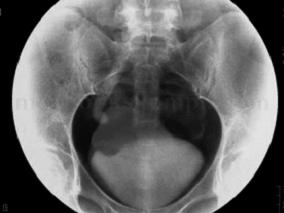

1小时条评论【病例资料】 患者男性,54岁。 主诉:左下腹痛1个月。 现病史:患者2009年2月8日晚无明显诱因出现左下腹绞痛,无放射,不伴腹泻、恶心、呕吐、发热,与体位、进食无明显关系。2009年2月9日于我院急诊就诊,查肾功能Cr 168mu;mol/L,B超提示左肾积水,左侧输尿管...